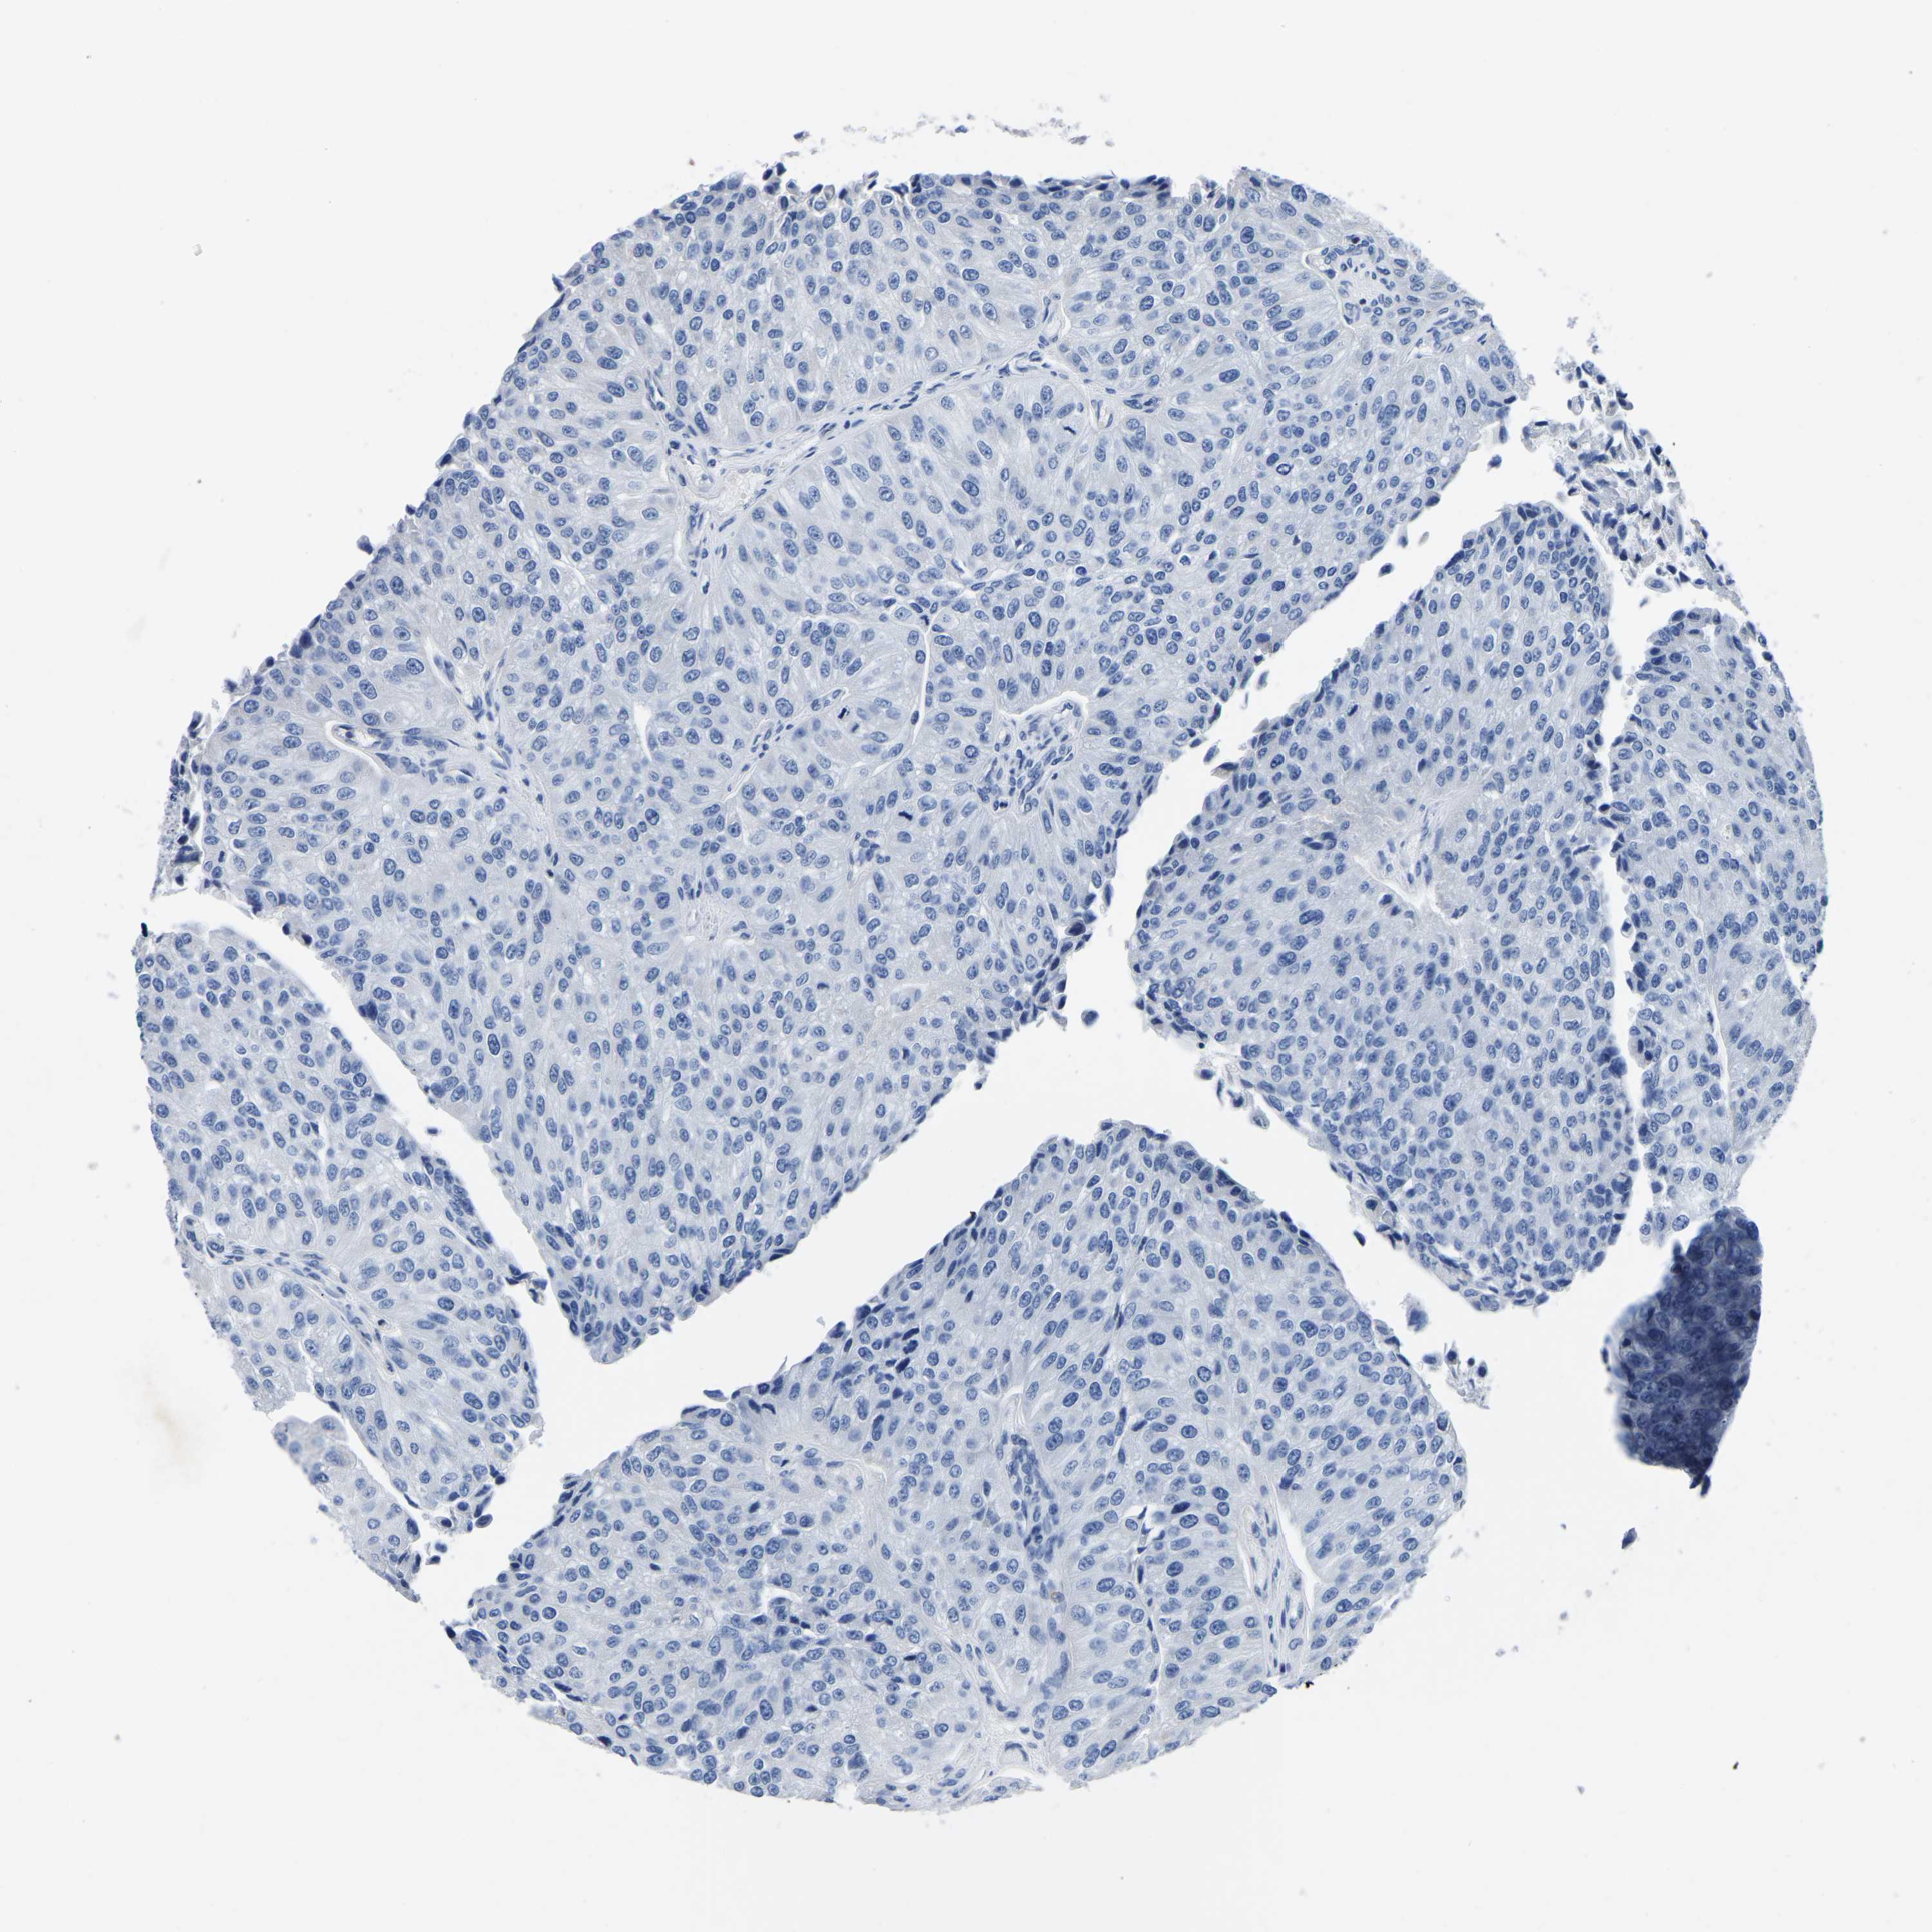

UROTHELIAL CANCER - Protein expressioni

A mouse-over function shows sample information and annotation data. Click on an image to view it in a full screen mode. Samples can be filtered based on level of antibody staining by selecting one or several of the following categories: high, medium, low and not detected. The assay and annotation is described here.

Note that samples used for immunohistochemistry by the Human Protein Atlas do not correspond to samples in the TCGA dataset.

Antibody stainingi

Antibody staining in the annotated cell types in the current human tissue is reported as not detected, low, medium, or high, based on conventional immunohistochemistry profiling in selected tissues. This score is based on the combination of the staining intensity and fraction of stained cells.

Each image is clickable and will lead to virtual microscopy that enables deeper exploration of all samples and also displays staining intensity scores, fraction scores and subcellular localization as well as patient and tissue information for each sample.

Antibody HPA014536

Antibody HPA019191

Staining

High

Medium

Low

Not detected

Intensity

Strong

Moderate

Weak

Negative

Quantity

>75%

75%-25%

<25%

None

Location

Nuclear

Cytoplasmic/membranous

Cytoplasmic/membranous,nuclear

Urothelial carcinoma, Low grade

Urothelial carcinoma, High grade